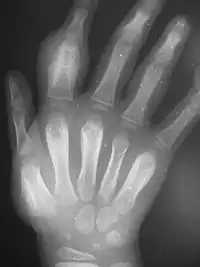

Secondary yaws typically shows widespread skin lesions that vary in appearance, including "crab yaws" (areas of skin of abnormal colour) on the palms of the hands and soles of the feet[13] (named for the crab-like gait they cause people with painful soles to assume[2]). These may show desquamation. These secondary lesions frequently ulcerate and are then highly infectious, but heal after 6 months or more.

Secondary yaws affects the skin and bones.[13] The most common bone-related problem is periostitis, an inflammation around the bone, often occurs in the bones of the fingers and the long bones of the lower arms and legs, causing swollen fingers and limbs.[13] This causes pain at night and thickening of the affected bones (periostitis).[2] About 75% of infected children surveyed in Papua New Guinea reported joint pain.[2] Swollen lymph nodes, fever, and malaise are also common.[13]